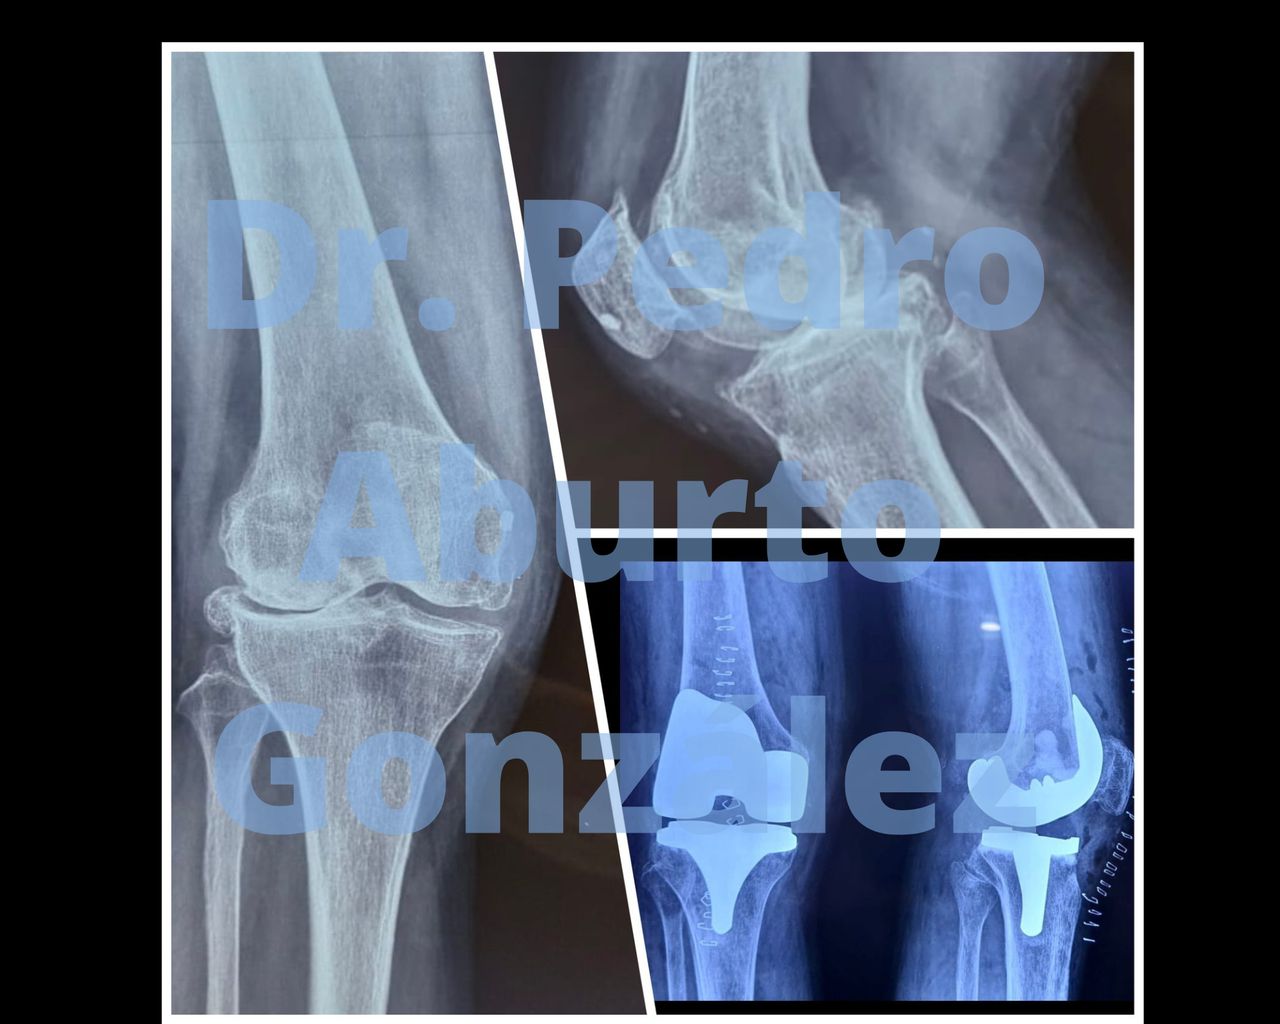

Pedro Aburto González

Traumatólogo

Ortopedista

Hola. Soy el Dr. Pedro Aburto González. Soy médico especialista en Traumatología y Ortopedia. Sé lo importante que es la salud para cada uno de nosotros. Será un gusto poder ayudarte a prevenir, detectar, curar y controlar los padecimientos a los que nos enfrentamos día a día.

- Lesiones de Menisco

- Lesiones de cartílago articular

- Lesión de Ligamentarias de Rodilla

Reconstrucción ligamentos cruzados de rodilla